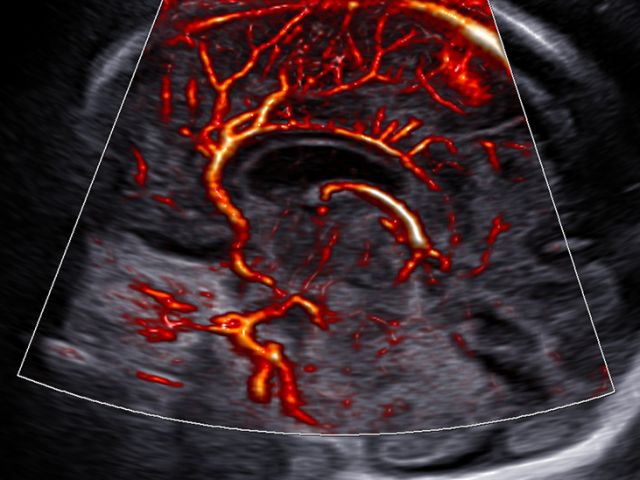

The color imaging performance has been improved to clearly visualize the hemodynamics of the blood flow. A greater sensitivity resulting from new color signal processing and a realistic 3D visualization of blood flow help understand the microcirculatory blood flows, accurate detection of peripheral blood vessels, and volumes of slow blood flows.

LumiFlow™ is a function that visualizes blood flow in three dimensional-like to help understand the structure of blood flow and small vessels intuitively.

MV-Flow™ visualizes microcirculatory and slow blood flow to display the intensity of blood flow in color. It is suitable for observation of microcirculatory blood flow and volume of slow blood flow.

The function uses directional power Doppler technology, enabling you to examine even the peripheral vessels. It displays information on the intensity and direction of blood flow.